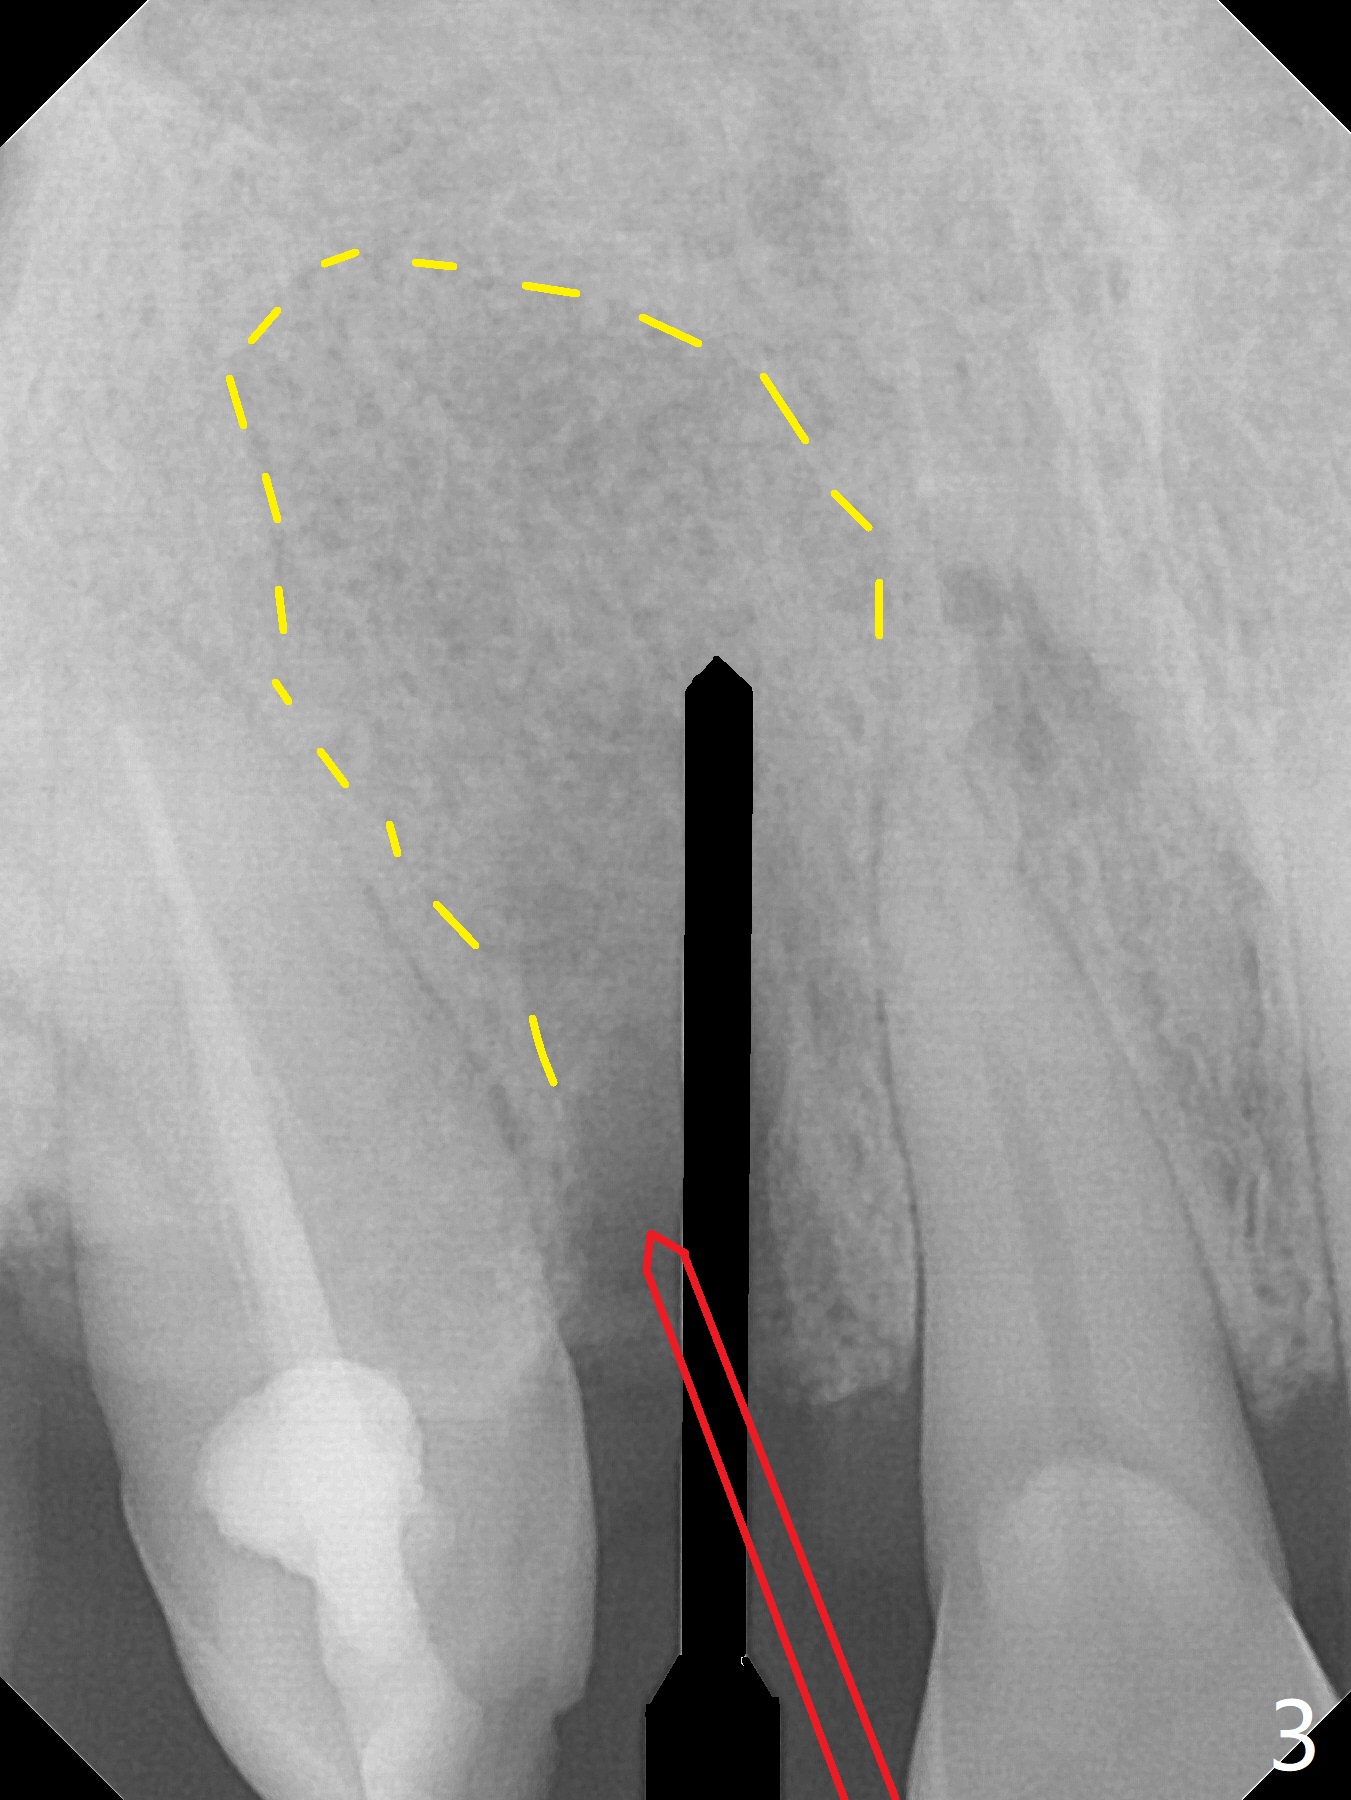

An apical abscess is present when the patient returns for immediate implant at #7 (Fig.1 *); a 2nd challenge is deep bite. After smooth extraction, the apical buccal plate is found to be perforated. Following debridement, a piece of gauze is placed in the apical defect for hemostasis, while osteotomy is initiated palatal (Fig.2). The apical defect seems to be extensive (Fig.3 yellow dashed line). A new trajectory is intended (red arrow) without much success. Before implant placement, bone graft is placed in the apical defect defect area, while a drill (Fig.4 D) is inserted in the finished osteotomy (Fig.5 O). In spite of seemingly large apical defect, the buccal crest bone exists (Fig.4 x). A 3x14(2) mm 1-piece implant is placed with stability; the first round of bone graft is apparently around the apical portion of the implant (Fig.6 *). The coronal end of the implant has to be adjusted several times buccopalatally to accommodate the deep bite. A 2nd round of bone graft following an immediate provisional closes the coronal space of the socket (Fig.7 *). CT will be taken to show the bone graft to repair the buccal plate defect when the patient returns for postop follow-up. In fact the defect is minimal in CT a month ago. The fistula does not disappear 1 week postop, but it is non tender (Fig.8). The patient complains of asymptomatic swelling in the right nostril. CT shows that the large buccal perforation is repaired with large amount of bone graft (Fig.9,10 *). It would be nicer to place the implant slightly more buccal apically (Fig.11 red lines; Fig.12 (preop design)). The buccoapical fistula disappears nearly 1 month postop (Fig.13). The apparently "lifeless" bone graft seems to be harmonious with the surrounding tissue (Fig.14). The periimplant gap reopens with implant mobility nearly 4 months postop (Fig.15), which is related to micro-movement associated with the immediate provisional. The latter is removed. A larger 2-piece implant will be placed in a 2-staged manner if needed (Fig.16). In fact the 3x14 mm straight 1-piece implant (Fig.17) has no mobility when it is retightened, but the trajectory remains buccal. Incision shows that there is no implant thread exposure. A 3x14 mm 15 degree angled 1-piece dummy implant is able to establish the correct trajectory, but there is no occlusal clearance (Fig.18). Micromovement during osteointegration may recreate loosening. Finally using Lindamann bur, the osteotomy is changed so that a 3.5x13 mm 2-piece implant does not need an angled abutment to establish occlusion (Fig.19). There is one palatal thread exposure. Allograft is placed circumferentially, followed by Human Amnion-Chorion Allograft and Collagen Plug. The wound does not heal 8 days postop (Fig.20), as related to the age (79 years old)? The wound appears to heal with a membrane on the surface (Amnion-Chorion one?) 3 weeks postop (Fig.21). The ridge looks wide 3.5 months postop (Fig.22,23). A 4.5x5.5(3) mm appears to be seated incompletely with a gap between the abutment and the implant (Fig.24<). A provisional is fabricated after heavy palatal reduction. Two months later, the provisional fractures. After repositioning the abutment with complete seating and torque (Fig.25), impression is taken. Although the buccal plate is concave, the gingiva remains healthy 10 months post cementation (Fig.26,27).